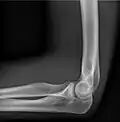

- Elbow - AP and Lateral. Radial head projections available on request

-

Lateral projection -

Anteroposterior projection -

Left elbow by 30 degrees internal oblique projection -

Left elbow by 30 degrees external oblique projection

- Soft tissues are seen with the same machine as for hard tissues, but a "softer" or less-penetrating X-ray beam is used. Tissues commonly imaged include the lungs and heart shadow in a chest X-ray, the air pattern of the bowel in abdominal X-rays, the soft tissues of the neck, the orbits by a skull X-ray before an MRI to check for radiopaque foreign bodies (especially metal), and of course the soft tissue shadows in X-rays of bony injuries are looked at by the radiologist for signs of hidden trauma (for example, the famous "fat pad" sign on a fractured elbow).